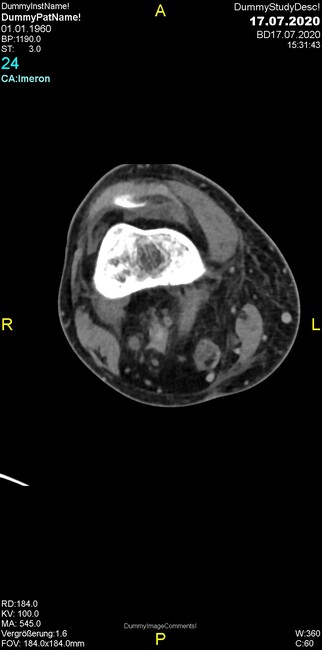

Um welche Modalitäten handelt es sich?

- Röntgen p.a. und lateral, CT coronar Knochenfenster, CT axial Weichgewebsfenster

- Röntgen p.a. und oblique, CT coronar Knochenfenster, CT axial Weichgewebsfenster

- Röntgen p.a. und lateral, CT sagittal Weichgewebsfenster, CT coronar Knochenfenster

- Röntgen p.a. und oblique, CT sagittal Knochenfenster, CT coronar Weichgewebsfenster

- Röntgen p.a. und lateral, CT coronar Weichgewebsfenster, MR axial

Was fällt in der CT im Knochenfenster auf?

- Weichgewebskalzifikationen lateral angrenzend an den Gelenkspalt